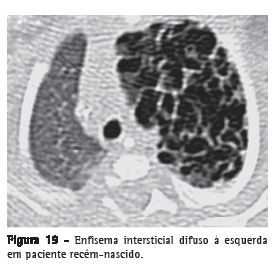

Enfisema intersticialDissecção do interstício pulmonar por ar, tipicamente localizado nos feixes broncovasculares, nos septos interlobulares e na pleura visceral, sendo mais frequentemente identificado em neonatos submetidos à ventilação mecânica (Figura 19). O enfisema intersticial dificilmente é reconhecido radiologicamente em adultos e é raramente identificado nos exames de TC. O processo expressa-se como áreas com densidade de ar com distribuição perivascular, peribroncovascular e/ou ao longo dos septos interlobulares (Figura 20), ou como áreas arredondadas de baixa atenuação simulando pequenas bolhas ou cistos (Figuras 19 e 20).(40,41)